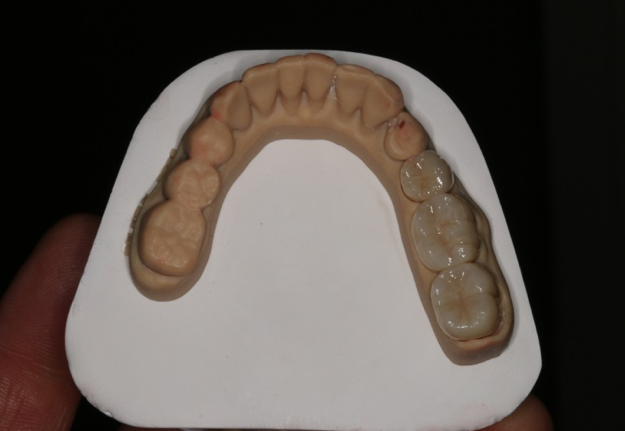

After completing an initial diagnostic appointment, a patient accepted three single-unit full-contour zirconia crowns that were milled from the digital impression and cut back for porcelain application. The application by a technician is analog dentistry. The ability of a dental laboratory to scan an analog crown-and-bridge impression is called converting an analog impression to a digital impression. The workflow after the conversion has become digitized. A dental model is virtually created with computer software, and a full crown proposal is fabricated for inspection virtually before the crown is milled (Figure 2). Due to the color of the digitized impression, the margins of the crown preparations are more easily and rapidly identified. The laboratory will also 3D print a working model, which will be used to develop the morphology of the final restoration by hand placement of porcelain (Figure 3). The decision to prescribe a full contour zirconia crown with cutback for porcelain application or complete full contour zirconia crowns lies solely on the attending dentist.9 A discussion with the patient before preparation of the teeth is imperative. After the discussion, the patient requested the zirconia copings with cutback and porcelain application for the posterior crowns (Figure 4 and Figure 5).

Fig 3. 3D-printed model.

Figure 3

Fig 4. Zirconia with cutback for porcelain application.

Figure 4

Fig 5. Occlusal view of completed zirconia with porcelain application on teeth Nos. 29, 30, and 31.

Figure 5